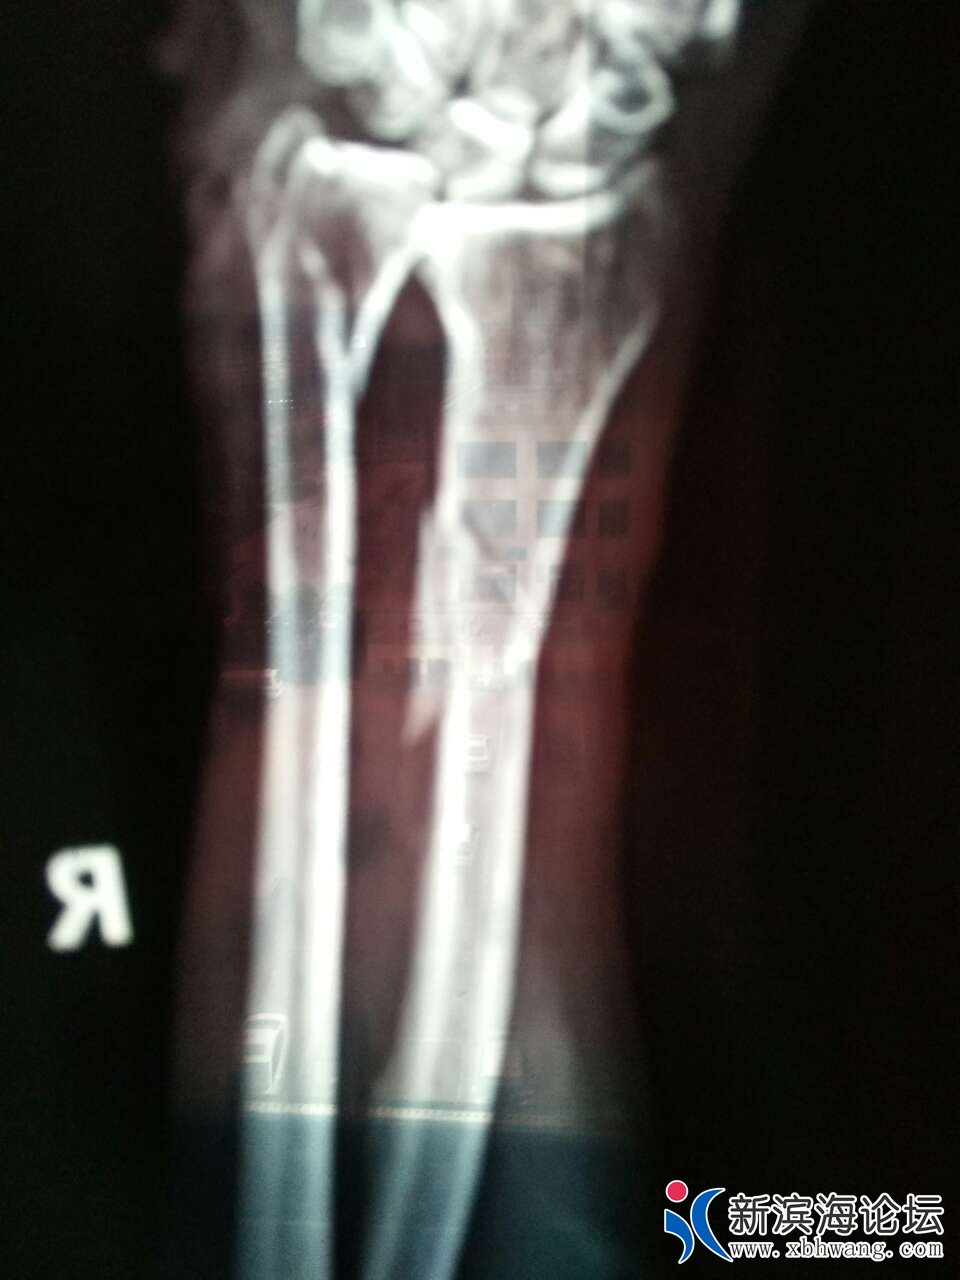

2019年06月28号供电局通知:《因新的变电所投运搭接施工,定于本月29(即星期六明天)全乡停电一天(早7点至晚7点,请看到的朋友相互轻告,提前做好停电准备工作。(注雨天顺廷)》这是原通知。由于搭线把380伏电接反了、导致动力电电机反转(天场乡、大套乡、所有380动力全部反转)造成人员伤害、导致手臂骨折,骨折四处手掌手臂多处撕裂伤。供电公司有没有责任?

这图惨不忍睹,看着都疼!供电公司应该负责